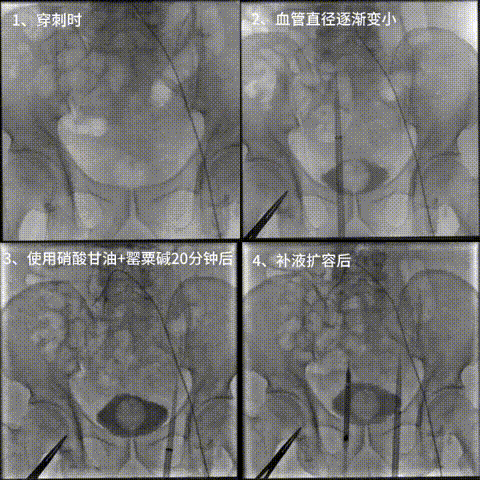

1.穿刺遇骼动脉及股动脉痉挛

6.gif